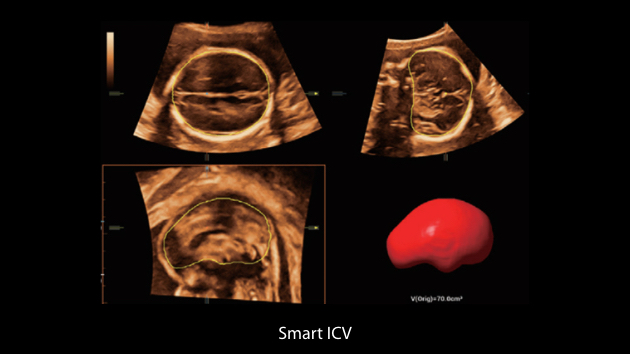

El sistema Nuewa I9, dise?ado exclusivamente para la atenciĂłn mĂ©dica neonatal y de mujeres, brinda una experiencia innovadora integral. Estas innovaciones se desarrollan sobre la base de un conocimiento profundo de situaciones clĂnicas complejas para proporcionar respuestas precisas y oportunas, una gran eficiencia y una experiencia de usuario extraordinaria.

La plataforma ZST+?es una innovaciĂłn extraordinaria que representa toda una evoluciĂłn en el ĂĄmbito de la ecografĂa. Transforma las mĂ©tricas ecogrĂĄficas de la formaciĂłn de haces convencional al procesamiento basado en datos de canal. Supera la limitaciĂłn tradicional de tener que equilibrar entre resoluciĂłn espacial, resoluciĂłn temporal y uniformidad del tejido, con lo que ofrece una calidad de imagen excepcional para soluciones de producciĂłn de imĂĄgenes infinitas con mejoras continuas.